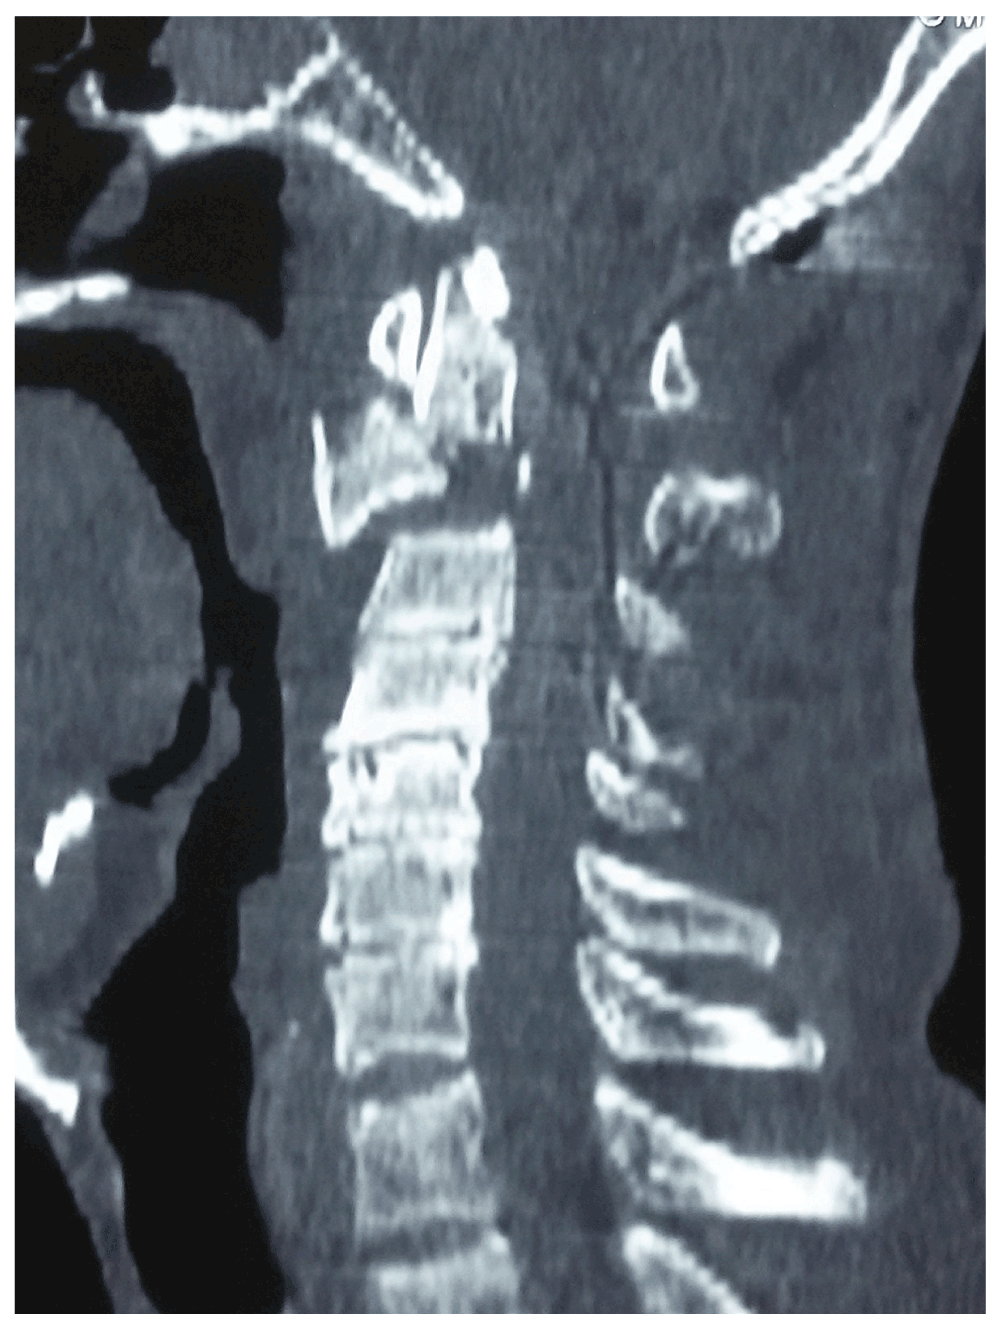

Spondylolisthesis surgery

Spondylolisthesis surgery image This image demonstrates Spondylolisthesis surgery.